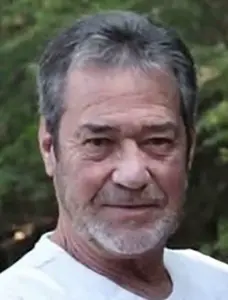

But for 63-year-old Frankie Thrasher, hiccups have become a relentless, life-altering ordeal.

Over the past five years, the Kentucky resident has endured relentless, unending spasms that have defied every traditional remedy, from holding his breath to surgical interventions.

His story is not just one of personal struggle, but a stark reminder of a medical condition that, while rare, can leave patients trapped in a cycle of pain and helplessness.

As healthcare systems worldwide grapple with rising emergency room congestion, Frankie’s plight underscores the urgent need for better understanding and treatment of intractable hiccups, a condition that has left him—and others like him—feeling like they are dying, one hiccup at a time.

Frankie’s hiccups began without warning, striking randomly and worsening over time.

What started as an occasional, annoying fit soon spiraled into a full-blown crisis.

At his worst, he recalls hiccups that lasted for days on end, sometimes even a full week, with no reprieve. ‘I was at my wits’ end,’ he says, describing the physical and emotional toll.

The spasms, which occur when the diaphragm contracts involuntarily, have left him gagging, spitting up white foam, and gasping for breath during episodes. ‘It feels like I’m dying,’ he says, his voice trembling.

The condition has upended his life, forcing him to cancel plans, avoid social gatherings, and live in constant fear that a single misstep—like a meal or a walk—could trigger another wave of hiccups.

The impact on his daily life is profound.

Frankie, a retired army veteran, now lives in a state of limbo, where every decision is clouded by uncertainty. ‘I can’t make future plans because it depends on whether I have hiccups that day,’ he explains.

Sleep is a distant memory; even lying down can trigger episodes.

His wife, Teina, a nurse, has become his primary caregiver, but even she admits the strain is overwhelming. ‘It’s not just physical,’ she says. ‘It’s the mental toll.

He’s exhausted, frustrated, and scared.’ Despite her medical training, Teina has struggled to find answers, as Frankie’s case has proven resistant to conventional treatments, including medications, dietary changes, and even surgery.

Medically, Frankie’s condition is classified as ‘intractable hiccups,’ a rare and perplexing disorder that can persist for months or even years.

Unlike typical hiccups, which resolve within minutes or hours, intractable cases often signal underlying issues, such as neurological disorders, metabolic imbalances, or even tumors.

In Frankie’s case, no clear cause has been identified, leaving doctors baffled.

His initial diagnosis came after two months of relentless hiccups, when his doctor labeled the condition as chronic, a label that has since become a curse rather than a clarification.

For Frankie, the situation is especially dire.

While home remedies like holding one’s breath or breathing into a paper bag may work for most, they are useless for someone whose hiccups have become a daily, unrelenting torment.

However, for patients like Frankie, who has been prescribed a range of medications including the epilepsy drug Neurontin, the journey to recovery is fraught with challenges.

Frankie’s journey with persistent hiccups is a testament to the desperation and complexity of managing this condition.

After exhausting online resources and joining various support groups, he tried a range of lifestyle remedies, including rapidly swallowing water, acupuncture, and drinking through a specially designed straw.

None of these approaches provided relief.

His treatment plan expanded to include prescription medications such as thorazine, a strong anti-psychotic used to treat intractable hiccups by interrupting the ‘hiccup arc’ in the brain.

Other medications, including Neurontin (gabapentin), Reglan (metoclopramide), baclofen, and Pepcid (famotidine), were also prescribed, but none worked for Frankie.

His condition continued to deteriorate, leaving him in a state of constant distress.

In a final attempt to address his condition, Frankie was referred for surgery to repair a hiatus hernia, which his doctor suspected might be exacerbating his hiccups.

However, the surgery did not provide the relief he hoped for.

Within days of the procedure, Frankie found himself hiccupping non-stop again, further deepening his sense of hopelessness.

Now, phrenic nerve surgery is his only remaining option, and he is awaiting a referral for a potential phrenic nerve block.

The thought of being alone during his worst hiccups haunts him, as he fears the possibility of being unable to call for help if he stops breathing.

Despite these challenges, Frankie remains determined, clinging to the hope that one day a cure will be found for this relentless and often misunderstood condition.